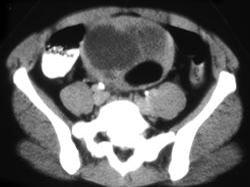

45岁女性患者,自觉腹部胀痛就诊,无发热,血象正常。B超提示左侧附件占位,行CT检查,如图所示,盆腔内见低密度肿块影,其内密度不均,最低CT值约为-150...

问题 45岁女性患者,自觉腹部胀痛就诊,无发热,血象正常。B超提示左侧附件占位,行CT检查,如图所示,盆腔内见低密度肿块影,其内密度不均,最低CT值约为-150.0hu。你认为最佳答案是 ( )

选项 A、卵巢异位妊娠 B、卵巢粘液癌 C、卵巢皮样囊肿 D、卵巢结核 E、卵巢粘液瘤

答案 C